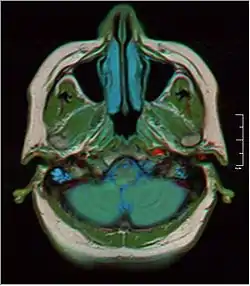

![]() MRI showing fluid in mastoid air cells | |